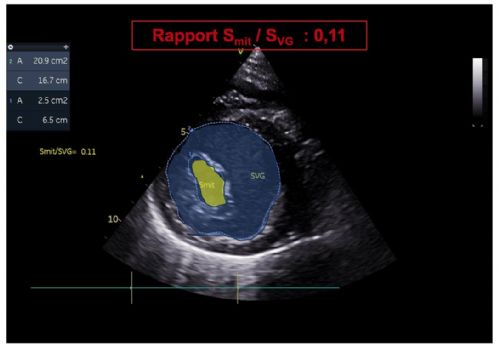

2. Une diminution du rapport de la surface de l'orifice mitral (Smit) sur la surface du ventricule gauche (SVG) en mésodiastole (Rapport Smit/SVG estimé entre 11 et 12 % selon les mesures ; VU chez le chien = 38 à 52 % selon O'Grady et coll., 1986) (Vidéo 6 et Figure 10).